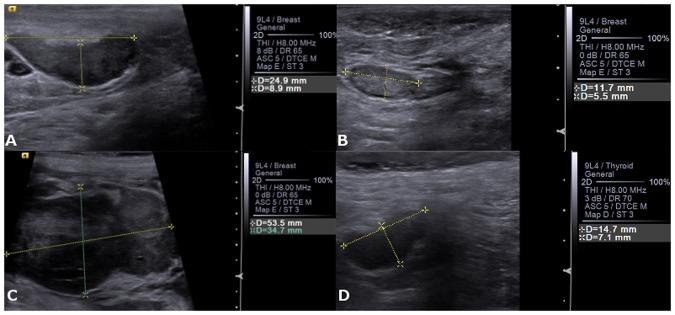

The aim of this study was to evaluate and compare the diagnostic accuracy of B-mode, Doppler ultrasonography and Acoustic Radiation Force Impulse (ARFI) elastography in the identification of axillary and inguinal lymph nodes metastasis in bitches with mammary neoplasms. The axillary (n = 96) and inguinal (n = 100) lymph nodes of 100 bitches were evaluated using B-Mode, Colour Doppler and ARFI-elastography. After this evaluation, mastectomy and lymph nodes excision were performed and these structures were histologically classified as free, reactive or metastatic. Ultrasonographic parameters were compared by Chi-Square or ANOVA tests and if they are significant, discriminative power analysis according to histopathological classification was performed (ROC analysis). The ARFI-elastography shear wave velocity (SWV) enabled metastasis identification in inguinal (sensitivity 95% specificity 87%) and axillary lymph nodes (sensitivity 100% specificity 94%). While B-Mode ultrasound Short/Long axis ratio evaluation of inguinal and axillary lymph nodes only resulted in a sensitivity around of 71% and specificity of 55%. In conclusion, B-Mode ultrasonography may contribute to diagnosis of metastasis in axillary and inguinal lymph nodes of bitches affected by mammary neoplasm with limited accuracy, while SWV evaluation proved to be an excellent diagnosis tool, which allows differentiation between free, reactive and tumour metastatic lymph nodes.

本研究旨在评估和比较 B 模式、多普勒超声和声辐射力脉冲(ARFI)弹性成像在鉴别患有乳腺肿瘤的母犬腋窝和腹股沟淋巴结转移方面的诊断准确性。使用 B 模式、彩色多普勒和 ARFI 弹性成像对 100 只母犬的腋窝(n=96)和腹股沟(n=100)淋巴结进行评估。评估后,对这些母犬进行了乳房切除术和淋巴结切除术,并对这些结构进行了组织学分类,分为游离、反应性或转移性。采用卡方检验或方差分析比较超声参数,如果有统计学意义,则根据组织病理学分类进行判别能力分析(ROC 分析)。ARFI 弹性成像的剪切波速度(SWV)能够识别腹股沟(敏感性 95%,特异性 87%)和腋窝淋巴结(敏感性 100%,特异性 94%)的转移。而 B 模式超声对腹股沟和腋窝淋巴结的短/长轴比评估仅导致敏感性约为 71%,特异性为 55%。总之,B 模式超声检查可能有助于诊断患有乳腺肿瘤的母犬的腋窝和腹股沟淋巴结转移,但准确性有限,而 SWV 评估被证明是一种出色的诊断工具,可区分游离、反应性和肿瘤转移性淋巴结。